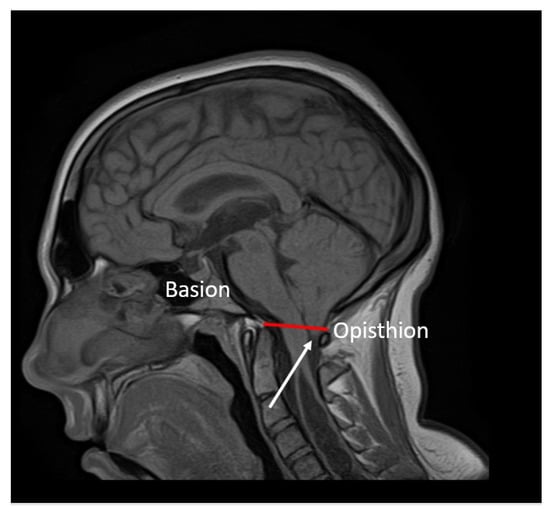

2.4. Neuroimaging